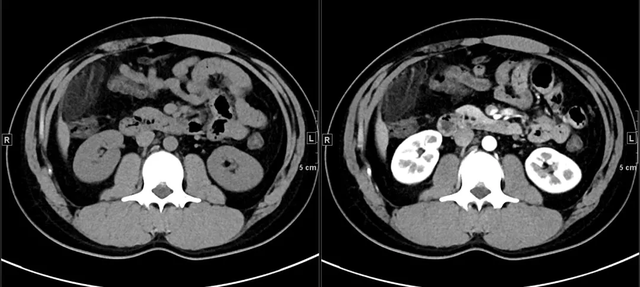

最后,做了腹盆增强CT。典型的男图像介绍如下:

上面4图分别为:平扫鼓像、动脉有啥期、门脉期、延迟期

影像表现:于升结肠前方可见一不规则团块状脂肪密度影,周围怀孕脂肪密度增高,升结肠周围可见饱满淋巴结,邻近肠壁有轻微增厚,无明显脓肿及肠梗阻征象。

诊断:升结肠肠脂垂炎在什么。